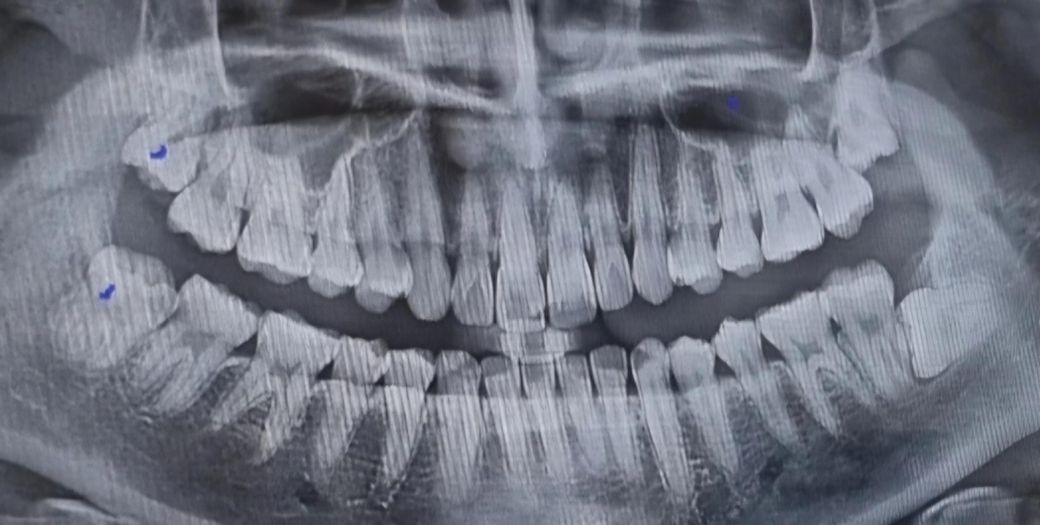

아프지 않은 사랑니 꼭 뽑아야 할까요?

오른쪽(사진에 점 찍힌 거)은 자꾸 옆쪽에 닿고 좀 아파서 위아래 둘다 발치를 했는데요 왼쪽은 아프지도 않고 좀 애가 누워있고 좀 무섭게 나있어서 안 뽑고싶은데 꼭 뽑아야하는 위치인지 확인 부탁드려요... 사랑니 뽑고 관리도 너무 힘들고 왼쪽은 아프지도 않은데 꼭 뽑아야할까요? 너무 무서워요......

왼쪽(사진상 오른쪽) 사랑니도 옆 멀쩡한 어금니에 영향을 주어 충치를 유발하거나 뿌리를 흡수시킬 가능성도 있으며 사랑니 주위로 낭이 형성될 수도 있습니다. 일반적으로 이런 경우 의학적으로 발치를 권장드리긴 하나 어디까지나 발치여부는 환자분 선택입니다.

지금당장 아프지 않더라도 기울어져 있는 사랑니는 앞의 어금니를 서서히 상하게 하여, 나중에 두개의 치아 모두 발치해야 할수 있습니다. 따라서 빠른시일내에 누워있는사랑니 발치를 권합니다.